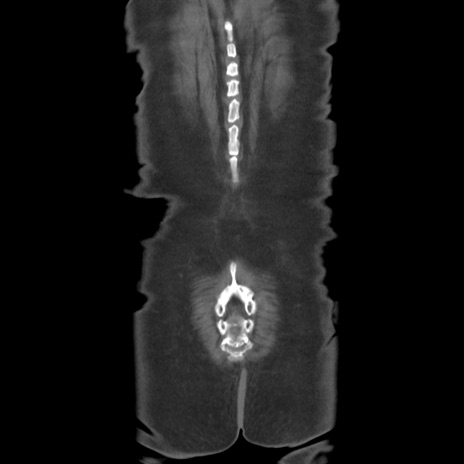

横断像

【症例】80歳代女性

【主訴】下腹部痛

【現病歴】約8時間前より下腹部痛の出現あり、救急外来受診。

【既往歴】両側付属器切除

【身体所見】意識清明、下腹部正中に手術痕あり、その部位に一致して圧痛と反跳痛あり。腸蠕動音は亢進。

【データ】WBC 9300、CRP 0.15